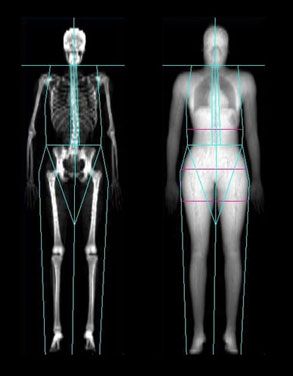

6. Densitometria óssea. “Depois dos 50 anos, ou ainda mais cedo dependendo do histórico familiar, é recomendável realizar o exame de densitometria óssea a cada dois anos para se prevenir da osteoporose, que é uma doença silenciosa e ainda assim bastante agressiva para com a terceira idade, quando uma fratura pode comprometer totalmente a qualidade de vida da paciente.”